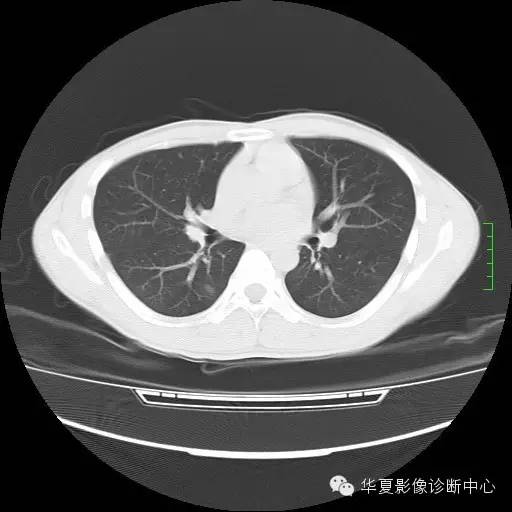

治疗后复查CT平扫:原两肺外围多发结节消失,右下肺新出现结节